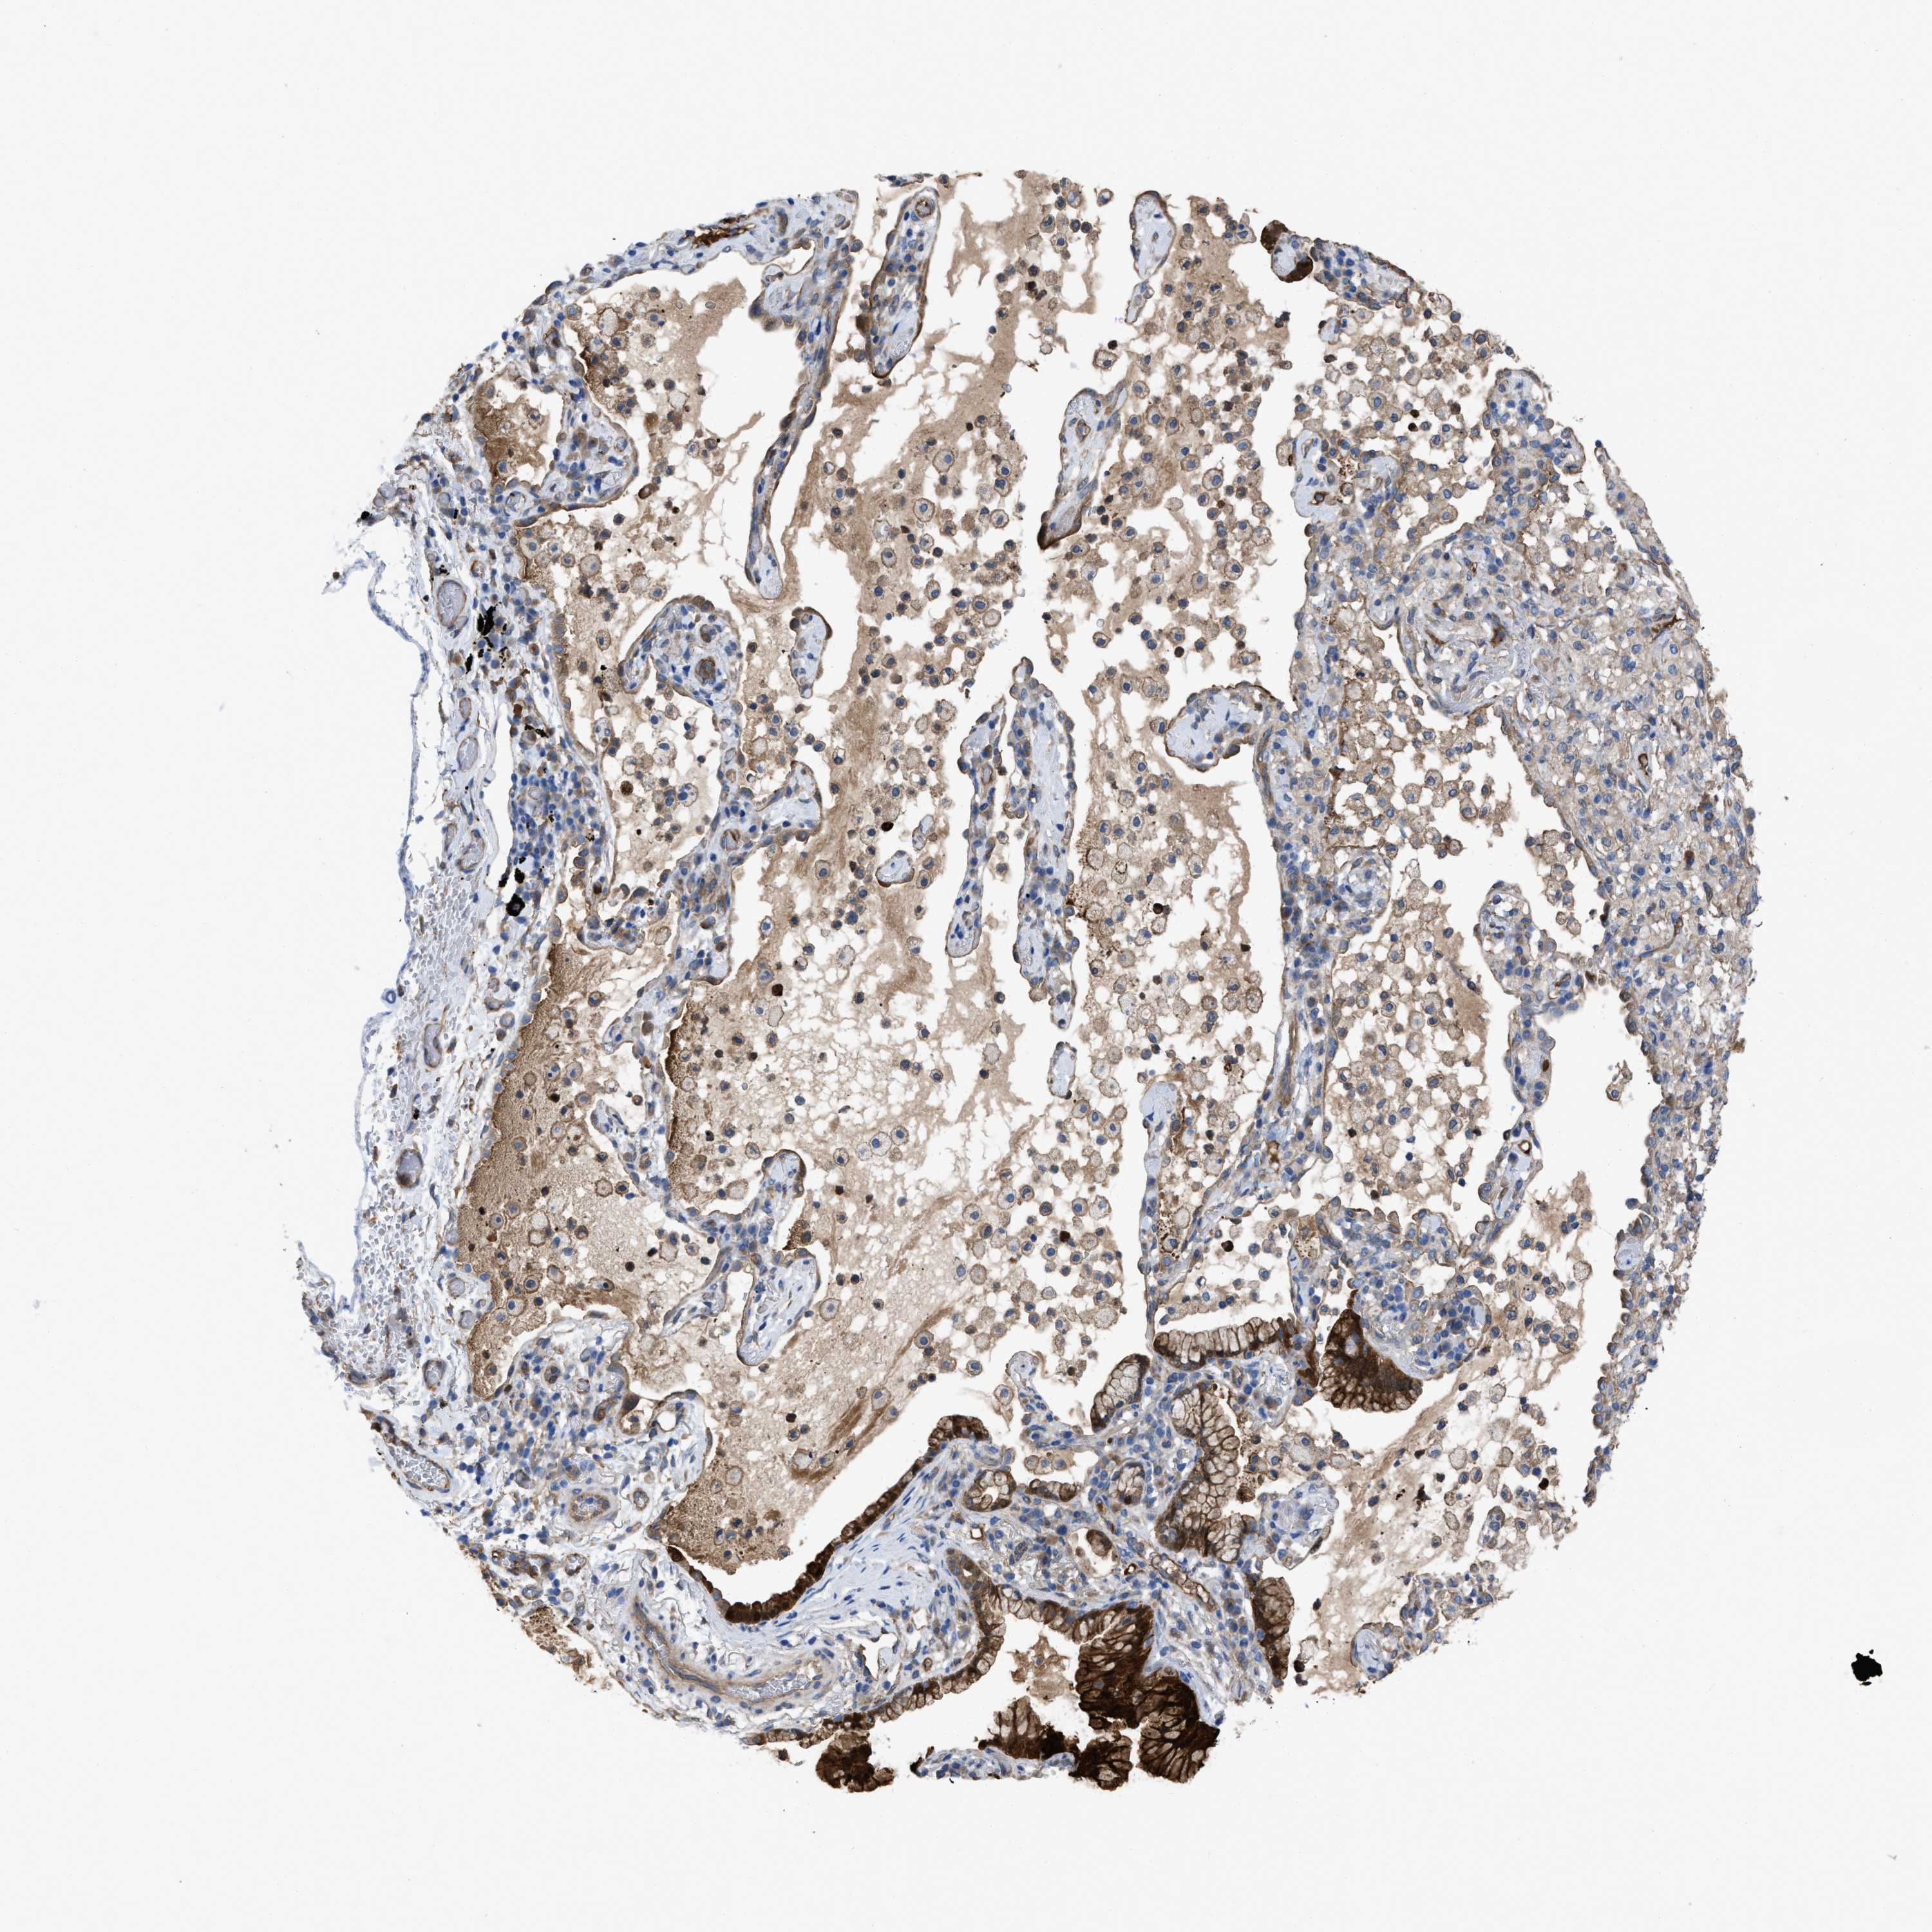

LUNG ADENOCARCINOMA (TCGA) - Interactive survival scatter ploti

The Survival Scatter plot shows the clinical status (i.e. dead or alive) for all individuals in the patient cohort, based on the same data that underlies the corresponding Kaplan-Meier plots. Patients that are alive at last time for follow-up are shown in blue and patients who have died during the study are shown in red.

The x-axis shows the expression levels (FPKM) of the investigated gene in the tumor tissue at the time of diagnosis. The y-axis shows the follow-up time after diagnosis (years). Both axes are complimented with kernel density curves demonstrating the data density over the axes. The top density plot shows the expression levels (FPKM) distribution among dead (red) and alive patients (blue). The right density plot shows the data density of the survived years of dead patients with high and low expression levels respectively, stratified using the cutoff indicated by the vertical dashed line through the Survival Scatter plot. This cutoff is automatically defined based on the FPKM cutoff that minimizes the p-score. The cutoff can be changed by dragging the vertical line or by entering a cutoff value in the square labeled "Current cut-off".

Under the Survival Scatter plot the p-score landscape (black curve; left axis) is shown together with dead median separation (red curve; right axis). Dead median separation is the difference in median mRNA expression between patients who have died with high and low expression, respectively. It is calculated as follows: median FPKM expression of dead patients with high expression - median FPKM expression of dead patients with low expression. This is intended to aid the user in visually exploring custom cutoffs and the associated p-scores and dead median separation.

Individual patient data is displayed and can be filtered by clicking on one or more of the category buttons on the top of the page. Categories describing expression level and patient information include: high, low, alive, dead, female, male and tumor stages. The scale of the x-axis can be toggled between linear and log-scale by clicking on the "x log" button. Mouse-over function shows TCGA ID, patient information and mRNA expression (FPKM) for each patient.

& Survival analysisi

Kaplan-Meier plots summarize results from analysis of correlation between mRNA expression level and patient survival. Patients were divided based on level of expression into one of the two groups "low" (under cut off) or "high" (over cut off). X-axis shows time for survival (years) and y-axis shows the probability of survival, where 1.0 corresponds to 100 percent.

TRIOBP is not prognostic in Lung Adenocarcinoma (TCGA)

Current cut offi

Current cut-off shows the cut-off (FPKM) currently selected. It may be changed manually. When the current cut-off is changed, the vertical dashed line indicating cut-off, the interactive survival scatter plot and the Kaplan-Meier curve will be automatically adjusted to show results accordingly.

:

Best expression cut offi

Based on the FPKM value of each gene, patients were classified into two groups and association between prognosis (survival) and gene expression (FPKM) was examined. The best expression cut-off refers the FPKM value that yields maximal difference with regard to survival between the two groups at the lowest log-rank P-value. Best expression cut-off was selected based on survival analysis .

When clicking on this number, the vertical dashed line indicating cut-off, the interactive survival plot, and the Kaplan-Meier curve will be adjusted to show results based on the best expression cut-off.

: 37.01

Median expressioni

Median expression refers to the median FPKM value calculated based on the gene expression (FPKM) data from all patients in this dataset. When clicking on this number, the vertical dashed line indicating cut-off, the interactive survival plot, and the Kaplan-Meier curve will be adjusted to show results based on the median expression.

: N/A

Median follow up timei

Median follow up time refers to the median time (years) after diagnosis with this type of cancer, based on clinical data from all patients in this dataset.

P scorei

Log-rank P value for Kaplan-Meier plot showing results from analysis of correlation between mRNA expression level and patient survival.

N/A

5-year survival highi

5-year survival for patients with higher expression than the expression cutoff.

For melanoma and glioma, 3-year survival is shown.

5-year survival lowi

5-year survival for patients with lower expression than the expression cutoff.

TCGA RNA samplesi

RNA-seq data is reported as average FPKM (number Fragments Per Kilobase of exon per Million reads), generated by the The Cancer Genome Atlas (TCGA) .

Normal distribution across the dataset is visualized with box plots, shown as median and 25th and 75th percentiles. Points are displayed as outliers if they are above or below 1.5 times the interquartile range. FPKM values of the individual samples are presented next to the box plot.

Average pTPM 38.9

Number of samples 497